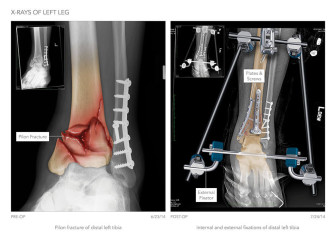

Placement of External Fixator and Right Sacral Fixation Screw